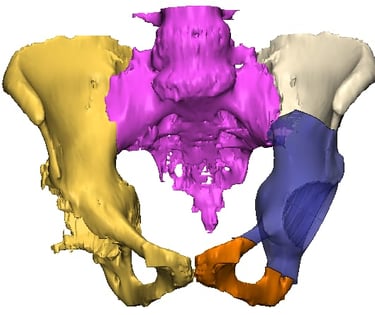

Galería Médica

Imágenes de procedimientos y técnicas en cirugía de cadera.